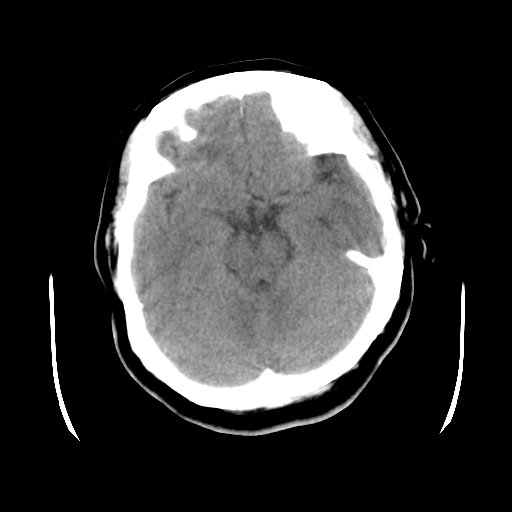

以下是引用cgf在2010-1-3 17:53:00的发言:[br]此病例多考虑:透明隔发育异常 透明隔囊肿可能性大;右侧基底节区(尾状核头)小片状低密度影考虑陈旧性腔梗[br][br]透明隔发育异常:包括透明隔间腔(第五脑室)、韦氏腔(第六脑室)、透明隔囊肿、透明隔缺如;前两者属于正常变异,后两者属于发育畸形;[br]透明隔间腔向下扩张形成韦氏腔;[br]有时透明隔间腔与透明隔囊肿很难鉴别;透明隔间腔间距一般不超过0.5cm,间距大于0.5cm时应考虑透明隔囊肿;[br]透明隔缺如为两侧脑室间隔缺如、融合成单脑室畸形,可伴有智力发育异常;[br][br]

以下是引用liaoqiang在2010-1-3 16:04:00的发言:[br]考虑侧脑室脉络丛囊肿?不除外变异的威氏腔。

以下是引用江广1996在2010-1-3 20:17:00的发言:[br]考虑变异的威氏腔。不除外侧脑室脉络丛囊肿.[br]透明隔囊肿大多数偏前,在侧脑室前角之间。